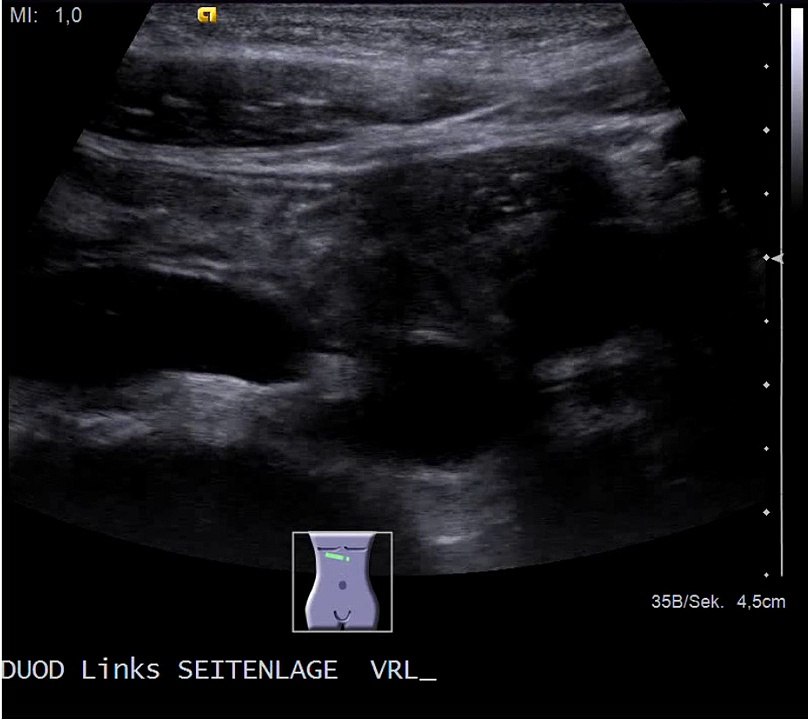

Erweiterter Angangsteil des Zwölffingerdarms (Duodenums) bei Kompression dieses Darmabschnittes durch die darüberliegende obere Darmarterie (Arteria mesenterica superior). Dadurch behinderter Nahrungstransport (Wilkie-Syndrom, Arteria mesenterica superior-Syndrom, AMS)